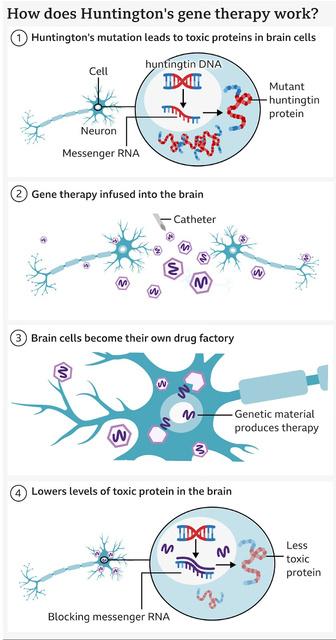

Huntington’s disease is a rare and inherited brain disorder, which is caused by a mutated allele, which produces a toxic protein. This protein then gradually damages cells in the brain - leading to problems with movement, thinking and behaviour. Normally, it begins in mid-adulthood and gradually gets worse over many years.

Scientists at the world-renowned University College London, collaborated alongside the biotech firm uniQure in a monumental development. The team have managed to successfully treat Huntington’s disease for the first time using an experimental gene therapy called AMT-130.

The trial took 3 years, and involved 29 patients. Those who received high doses of the therapy saw the disease progression slow by roughly 75% in comparison to the projected rates. The treatment plan uses a modified virus to deliver a strand of therapeutic DNA into brain cells to suppress the production of the huntingtin protein which is toxic and derives the disease.

To deliver the therapy, a complex method is employed, with the viral vector being infused into 2 regions of the brain over 12-20 hours. Despite there being some side effects such as central nervous system inflammation, which were then treated with steroids, they were mainly linked to the surgery.

For patients, these findings are a landmark in the treatment plan, as Huntington’s was for a long time considered incurable, yet may now be shifted into a treatable condition. UniQure has already taken the steps to bring this to hospitals - planning to seek regulatory approval in the United States in early 2026, and then in Europe and the UK in following years.